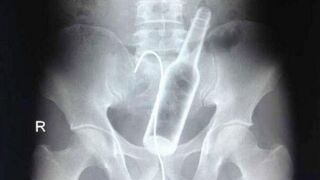

Man With Bottle Stuck Up His Butt Had No Clue How It Got There

A man who arrived at his local hospital complaining of stomach pains was found to have a bottle lodged deep inside his abdomen and no memory of how it got up there.